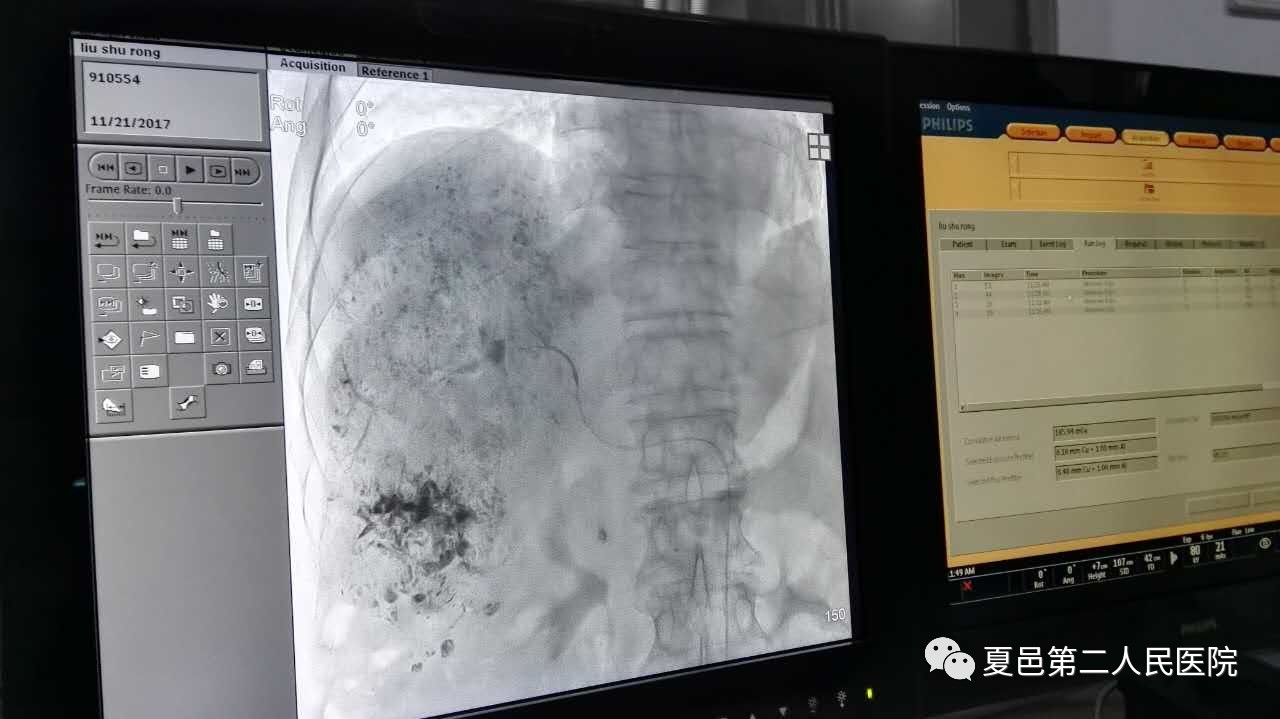

11月26日,夏邑县第二人民医院肿瘤内科温永胜医师在介入科医务人员的协助下,成功为56岁肝癌患者实施“经导管肝动脉造影栓塞术”。

11月26日下午,这是郭大叔第八次进行肝癌介入治疗了,走进夏邑二院介入中心,只见肿瘤内科温永胜医师在郭大叔股动脉插入一根极细的导丝,到达肝脏肿瘤部位,通过特殊的数字减影设备找到给肿瘤供血的动脉,然后把栓塞剂和化疗药物打到肿瘤部位,使其局部发挥作用。这样不仅使肿瘤供血动脉被堵塞,肿瘤失去了营养供应,还让化疗药物局部发挥药效,达到杀灭癌细胞的作用。